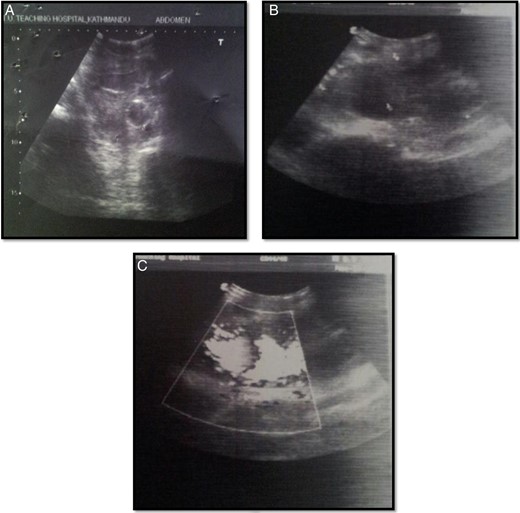

A 25-year-old HCV-positive male with a history of IV drug abuse for the past 3 years presented to our institution with complaint of pain lower abdomen and frank hematuria after receiving a minimal blow to his lower abdomen by his 4-year-old daughter during her play 6 days back. On arrival to our emergency room, the patient was conscious oriented tachycardic with a diffuse nonpainful nontender swelling in his right groin. Rest of his vitals and general examination was within normal limits. Distal pulsation in the right leg was present. His hemoglobin was 6.3 g% and CBC was high. Ultrasonogram of abdomen and pelvis revealed distended urinary bladder with clots and pseudoaneurysm of right common femoral artery measuring ∼112 × 69 × 87 mm (Fig. 1). The patient was planned for urinary bladder exploration along with evacuation of clot by urology team by cystoscopy after adequate resuscitation. During cystoscopy, nothing was visible due to massive clot inside the bladder which was incompletely evacuated so three-way Foley catheter was left in situ for continuous postoperative irrigation. Postoperatively, hematuria continued despite transfusion and, hence, emergent abdominal pelvic CT scan was performed.

Arterial Doppler pictures: (A) urinary bladder with Foley's in situ and echogenic content likely clots; (B) large solid-cystic pulsatile lesion noted in the right inguinal region; (C) lesion in connection with common femoral artery via wide neck which showed to and fro spectral wave form (classical Ying Yang flow).